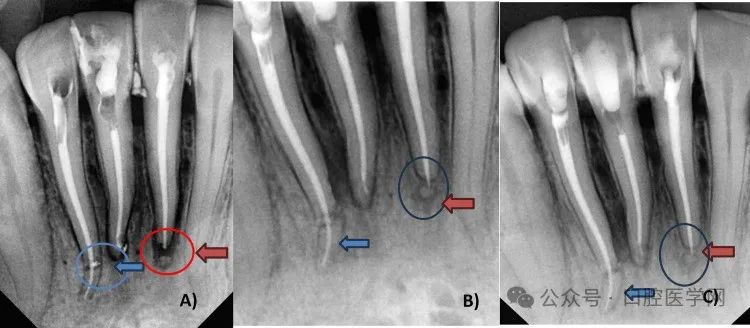

分别对31和42号牙根尖三分之一根折实施根管治疗。对两颗牙齿采用两种不同的非手术创伤处理方法(图4)。

图4. 下颌前牙创伤处理(根尖三分之一根折)

具体方法如下:初级技术中,31号牙保留根尖断端。首先对疼痛更明显的31和41号牙安排根管治疗。使用利多卡因(1:80000)麻醉,橡皮障隔离。为两颗中切牙开髓,用圆钻和Endo Z钻制备三角形髓腔入口。去除牙髓,使用6K、8K、10K、15K锉初步疏通,建立滑行通路。通过数字化放射片及根尖定位仪确定工作长度(31号牙25毫米,41号牙24毫米)。使用润滑剂(乙二胺四乙酸凝胶)配合2.5%次氯酸钠与生理盐水交替冲洗,将根管扩大至30K。使用K锉进行生物力学预备,配合电动马达手机振荡头。初诊时放置氢氧化钙封药。复诊时使用牙胶尖和AH Plus封闭剂(Dentsply)进行充填。采用热垂直加压技术,使用快速充填笔操作。右下中切牙存在侧支开口及唇侧弯曲,根尖部可见封闭剂溢出。左下中切牙根管充填至冠方断端24.3毫米处,未触及根尖断端。根管治疗后使用玻璃离子水门汀(GIC)修复(图5A-5B)。

图5. A) 31和41号牙根管治疗,31号牙保留根尖断端(圆圈及蓝色箭头),42号牙根尖三分之一根折(红色箭头);B) 42号牙冠方断端疏通(黑色箭头);C) 42号牙根折线(圆圈);D) 42号牙根尖断端疏通(红色箭头);E) 42号牙冠方至根尖断端通路

第二种方法采用非手术方式对42号牙冠方与根尖断端进行对位。最初对42号牙采取观察策略,但因患者主诉不适、疼痛及牙齿松动加重,决定实施非手术根管治疗重新连接冠方断端。遵循COVID-19防护措施、患者知情同意及防护技术。对患者实施麻醉,橡皮障隔离。制备髓腔入口,去除冠方断端牙髓。使用25毫米K锉在冠方断端建立初步疏通及滑行通路。冠方断端疏通及预备采用K锉配合电动马达手机振荡头(NSK)。首先仅预备冠方断端,建立直线通路,放置氢氧化钙封药。保留弯曲的根尖断端。三天后患者根管疼痛复发,药物治疗无效。再次检查放射片,推测根尖三分之一断端残留牙髓可能是疼痛持续原因。使用31毫米锉疏通根尖断端,采用直线通路进入牙根冠方至根尖断端。采用平衡力技术冠向下预备确保成形。通过根尖定位仪及影像学分析确定工作长度,使用根管测量尺测量。该牙工作长度约28.30毫米(图6)。

根管扩大使用10K、15K、20K、25K、35K系列K锉。操作时使用振荡头配合Endomate DT电动马达,所有锉转速40,扭矩0。每支锉使用后进行EDTA润滑、2.5%次氯酸钠及生理盐水冲洗。使用牙胶尖和AH Plus封闭剂进行充填。采用热垂直加压技术使用阻塞笔操作。最终使用GIC完成根管治疗后修复(图7)。